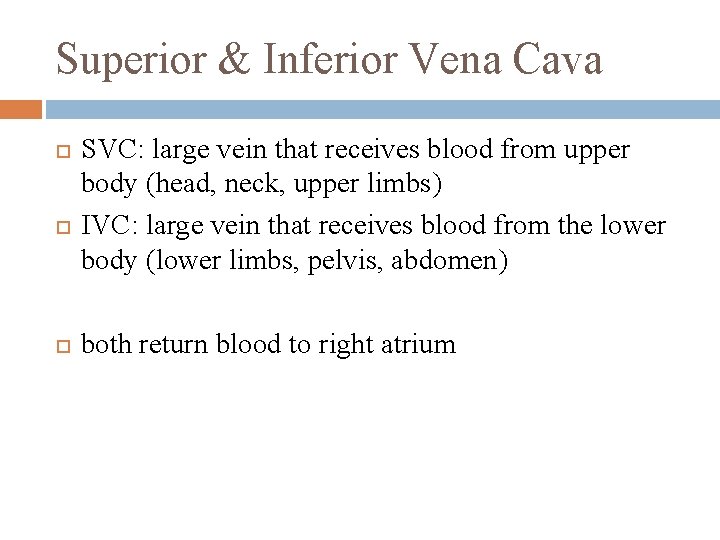

Superior & Inferior Vena Cava SVC: large vein that receives blood from upper body (head, neck, upper limbs) IVC: large vein that receives blood from the lower body (lower limbs, pelvis, abdomen) both return blood to right atrium